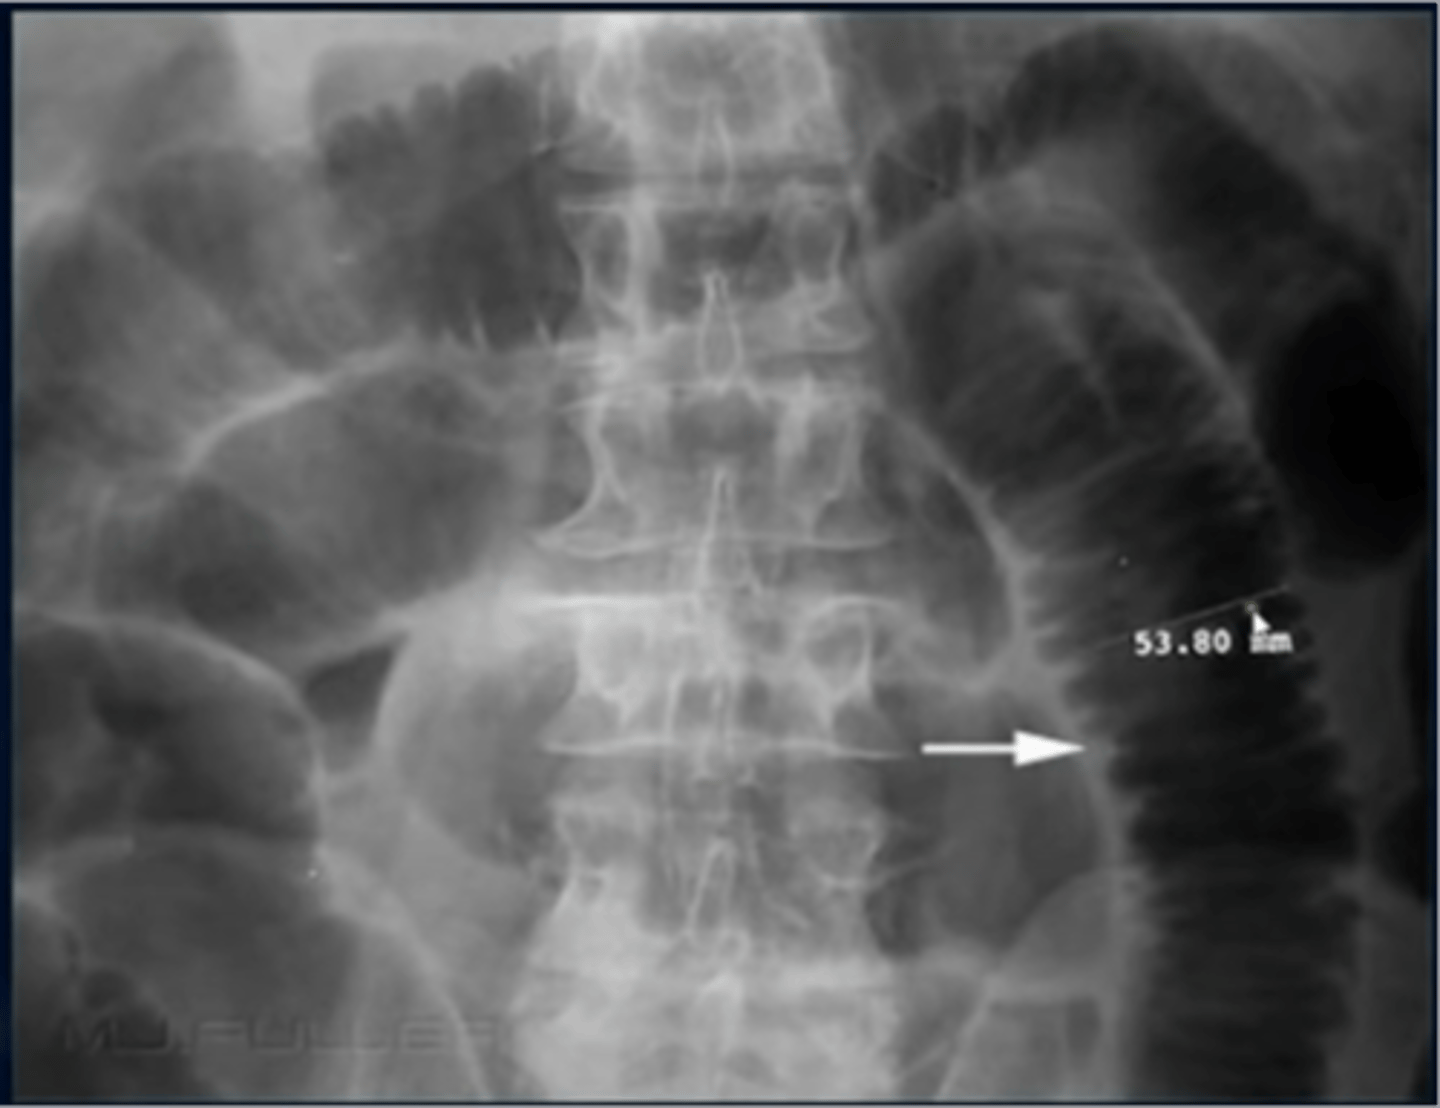

What is an abdominal aortic aneurysm (AAA)?

-enlargment of abdominal aorta

-Risk factors: HTN, atherosclerosis

-usually asymptomatic, but can cause pain

-large ones can rupture lead to hypotension and death

-get US to follow size, but if concerned about rupture GET CT

What is a calcified aortic aneurysm?

-common in those with DM

-aorta has rim like calcifications

-aneurysm is when normal diameter exceeds 50% of normal size